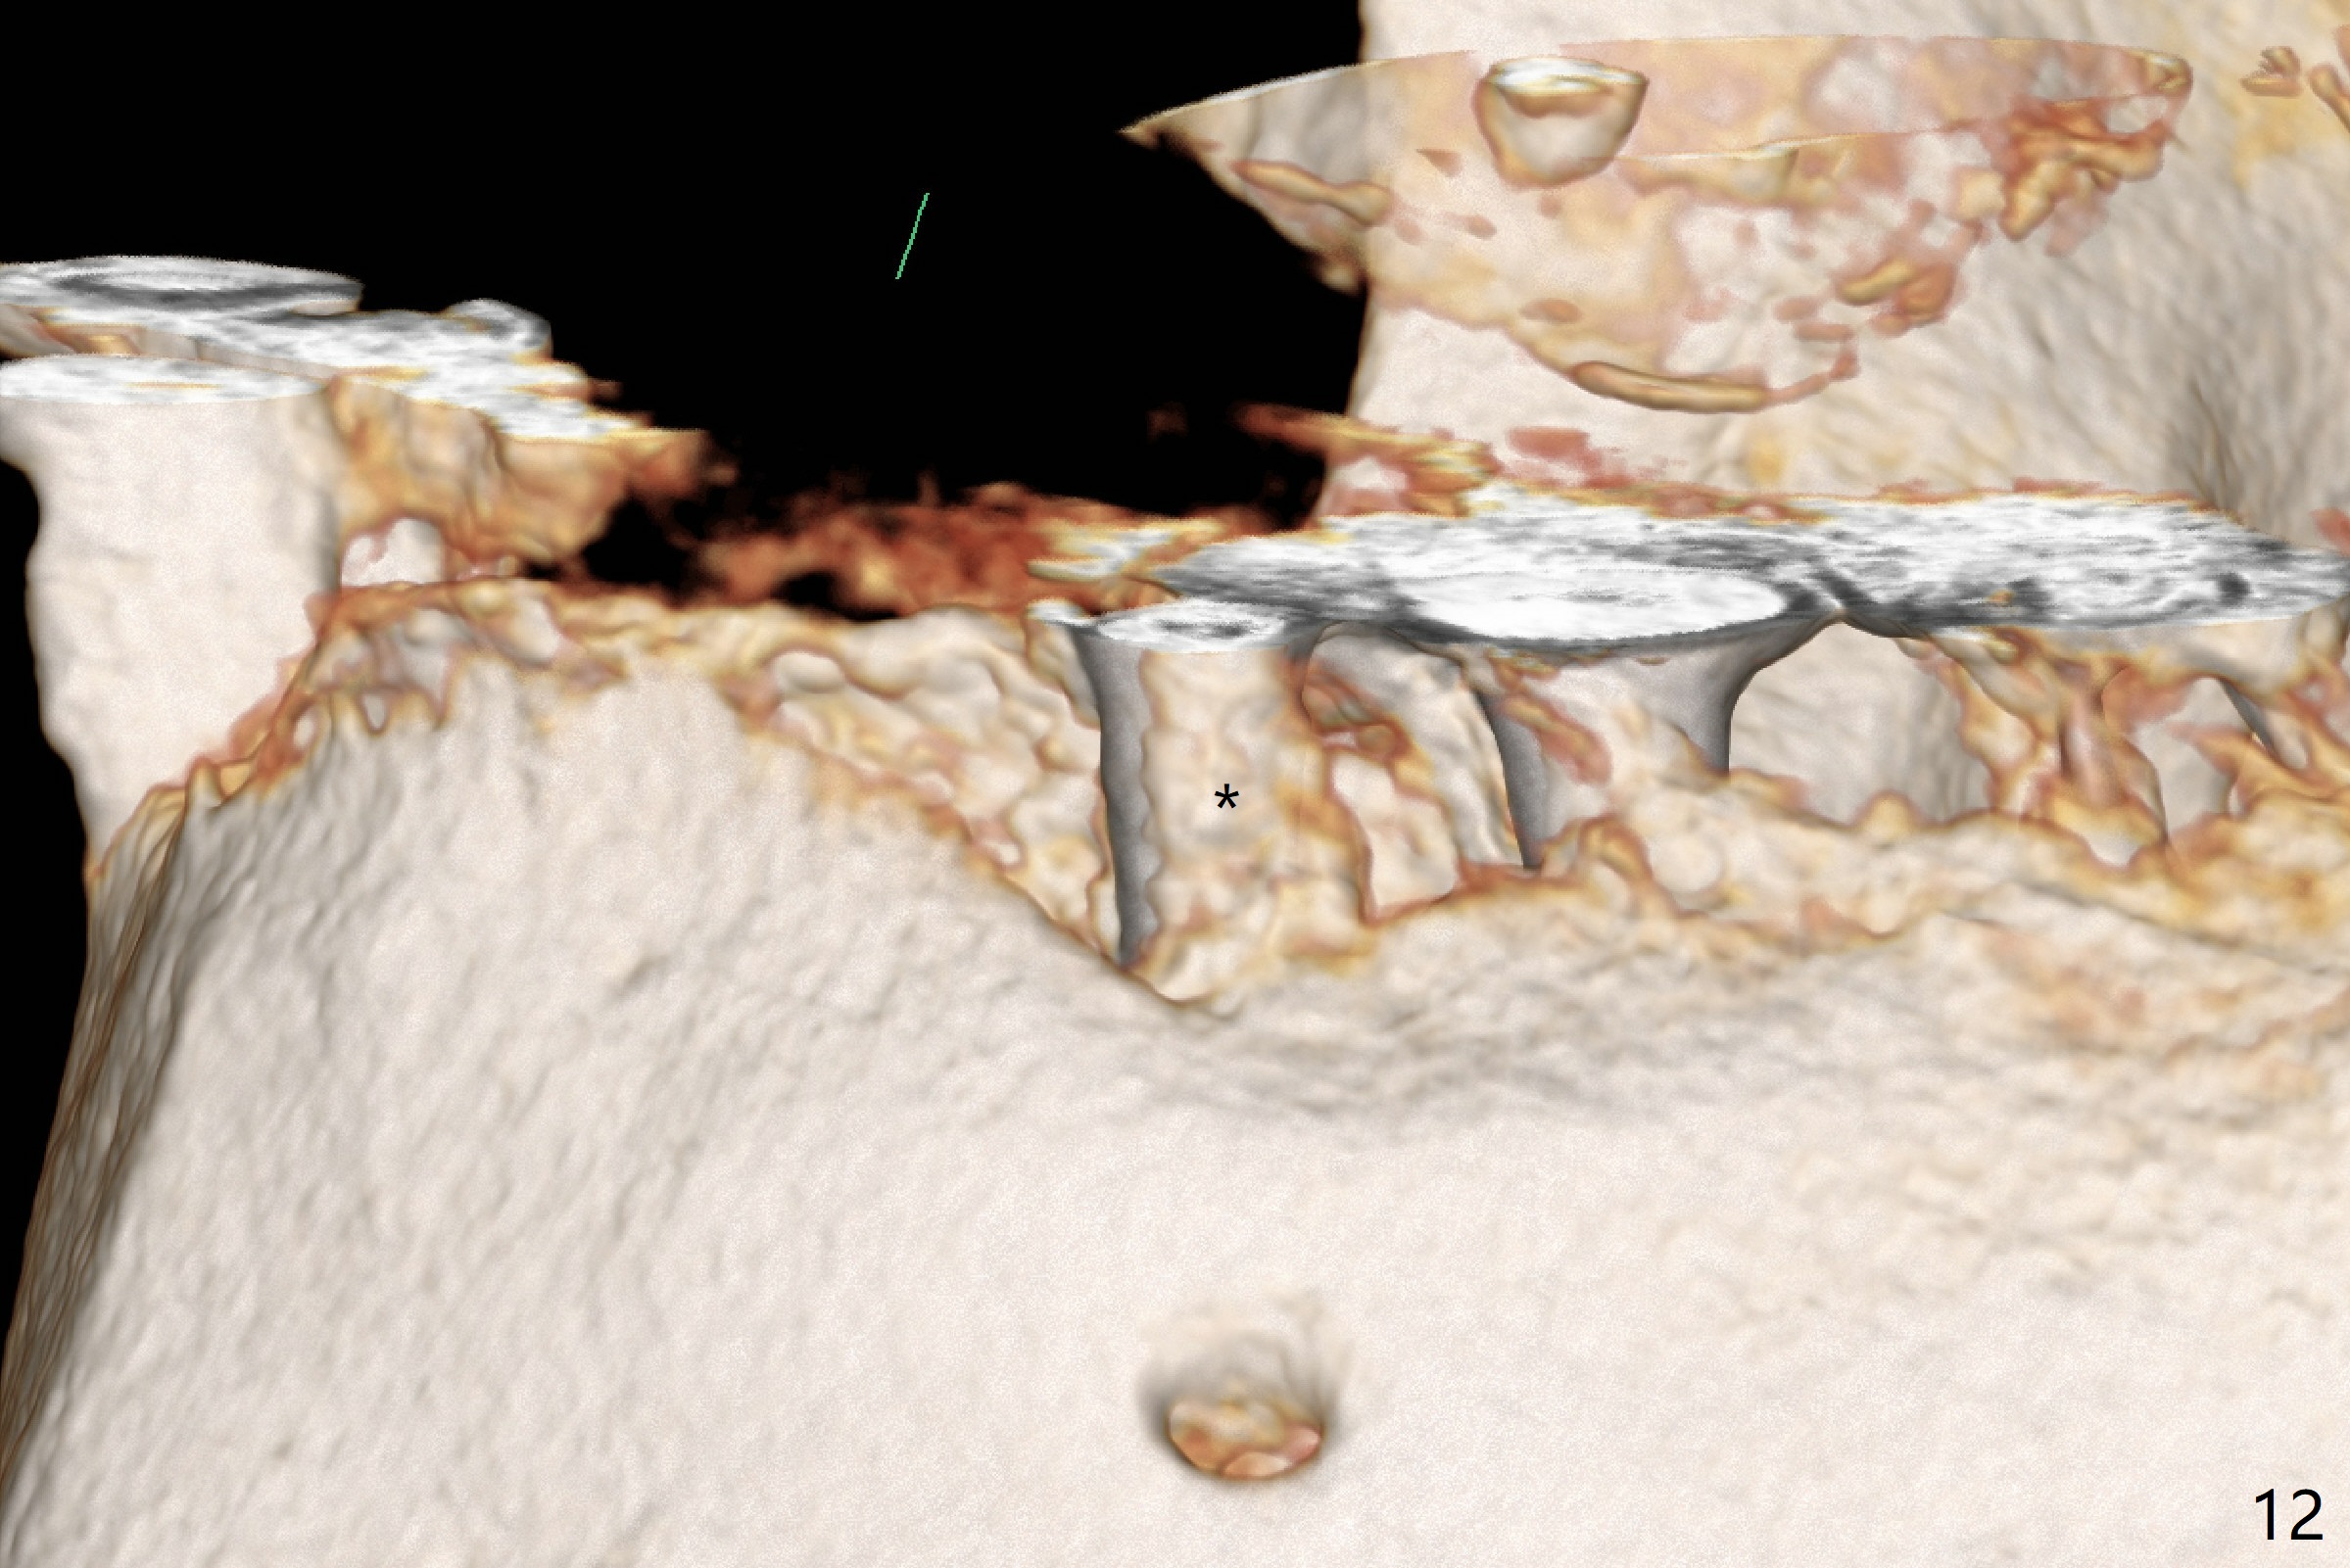

After removal of the pontic at #19 and retainer at #20 (Fig.1) and of vertically fractured root, the buccal plate is found to be defective (Fig.2 *). An implant will be placed as lingual as possible. Since the apex of the affected tooth is coronal to the Mental Loop (Fig.3 red dashed line), an osteotomy (Fig.4 yellow arrow) to be established in the mesial slope (blue dashed line) after extraction (black area) appears to be safer than that along the long axis of the tooth. The initial osteotomy is accomplished by free hand (Fig.5), but when the lower RPD is inserted, the superior end of the 1.5 mm pilot drill is distal (Fig.6). When the trajectory is corrected using the RPD as a surgical guide at the same depth (17 mm gingival level), brisk hemorrhage is from the osteotomy without severe pain. After hemostasis is achieved by packing the socket with Osteogen plug and bone graft and packing bone graft into the osteotomy, 3.3 mm Magic Drill is used for 14 mm. A 4x11 mm IBS implant is placed with 60 Ncm (Fig.7). The implant is then placed deeper, followed by placement of a 4.5x4(3) mm abutment and further bone graft (Fig.8). Finally the implant/abutment complex is apparently in an acceptable mesiodistal position with a large buccal gap which has been filled by bone graft (Fig.9 *). In fact the Mental Loop seems to have been not violated in the procedure (Fig.10). X-ray is taken 3 and 6 months postop. Bone graft (Fig.11,12 (CBCT) *) appears to remain over the buccal (B) surface of the implant coronally 13 months postop (7 months post cementation). The gingiva at #19 and 20 is apparently healthy 8 months post cementation except mild recession at #20 (Fig.13).